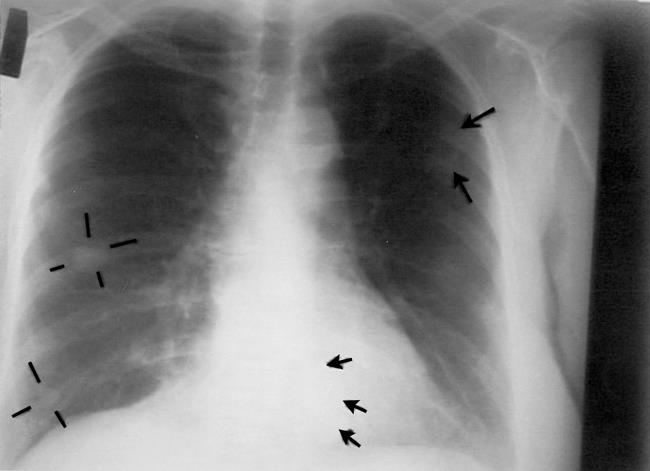

Three cases of unexpected long-term survival from severe cases of cancer have been documented after receiving intravenous vitamin C therapy. [Canadian Medical Assn. Journal March 28, 2006] (See photos below)

Image credits: Canadian Medical Association Inc.

Chest radiography, November 1996, about 1 month after intravenous vitamin C therapy was started. Cannonball lesions are evident in both lungs, as indicated by the arrows and lines.

Chest radiography, June 1997, showing shrinkage of tumor masses; the arrow indicates one residual abnormality.